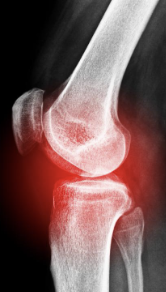

무릎 관절염 증상 원인 치료방법

무릎 관절염 증상 원인 치료방법 등 무릎 관절염과 관련된 정보를 알아보도록 하겠습니다. 무릎 관절은 우리 몸에서 가장 큰 관절로, 걷기, 뛰기, 오르내리기 등 매일 다양한 활동을 할 때 사용합니다. 그러나 무릎 관절은 부상이나 통증에 쉽게 영향을 받을 수 있으므로 적절한 관리와 운동이 필요합니다.